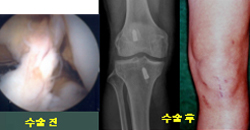

- 슬관절 반월상 연골판 파열

무릎 관절을 보호하는 연골판이 파열된 경우 관절경 수술로 관절이 손상되는 것을 예방합니다.